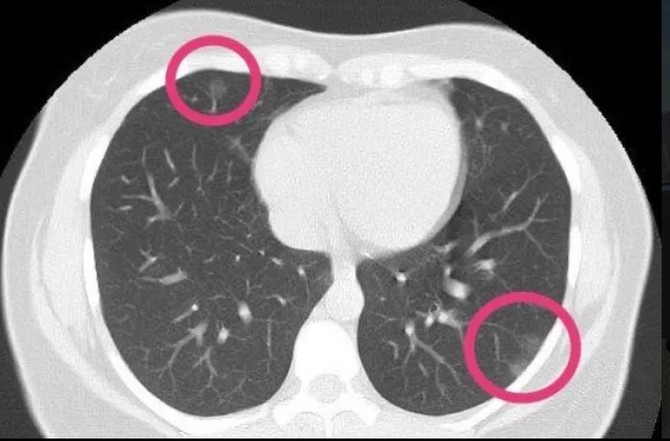

Ovo Je Ct Snimak Pluca Posle Teske Infekcije Evo Sta Korona Virus Moze Da Uraditi Plucima Zarazenog Pacijenta

Sokantan Snimak Pluca Zarazenih Od Koronavirusa Lekari Uocili Bele Senke Poput Mlecnog Stakla Foto

Skener 41 Godisnje Zene Najbolje Pokazuje Na Koji Nacin Korona Virus Unistava Nasa Pluca Telegraf Rs